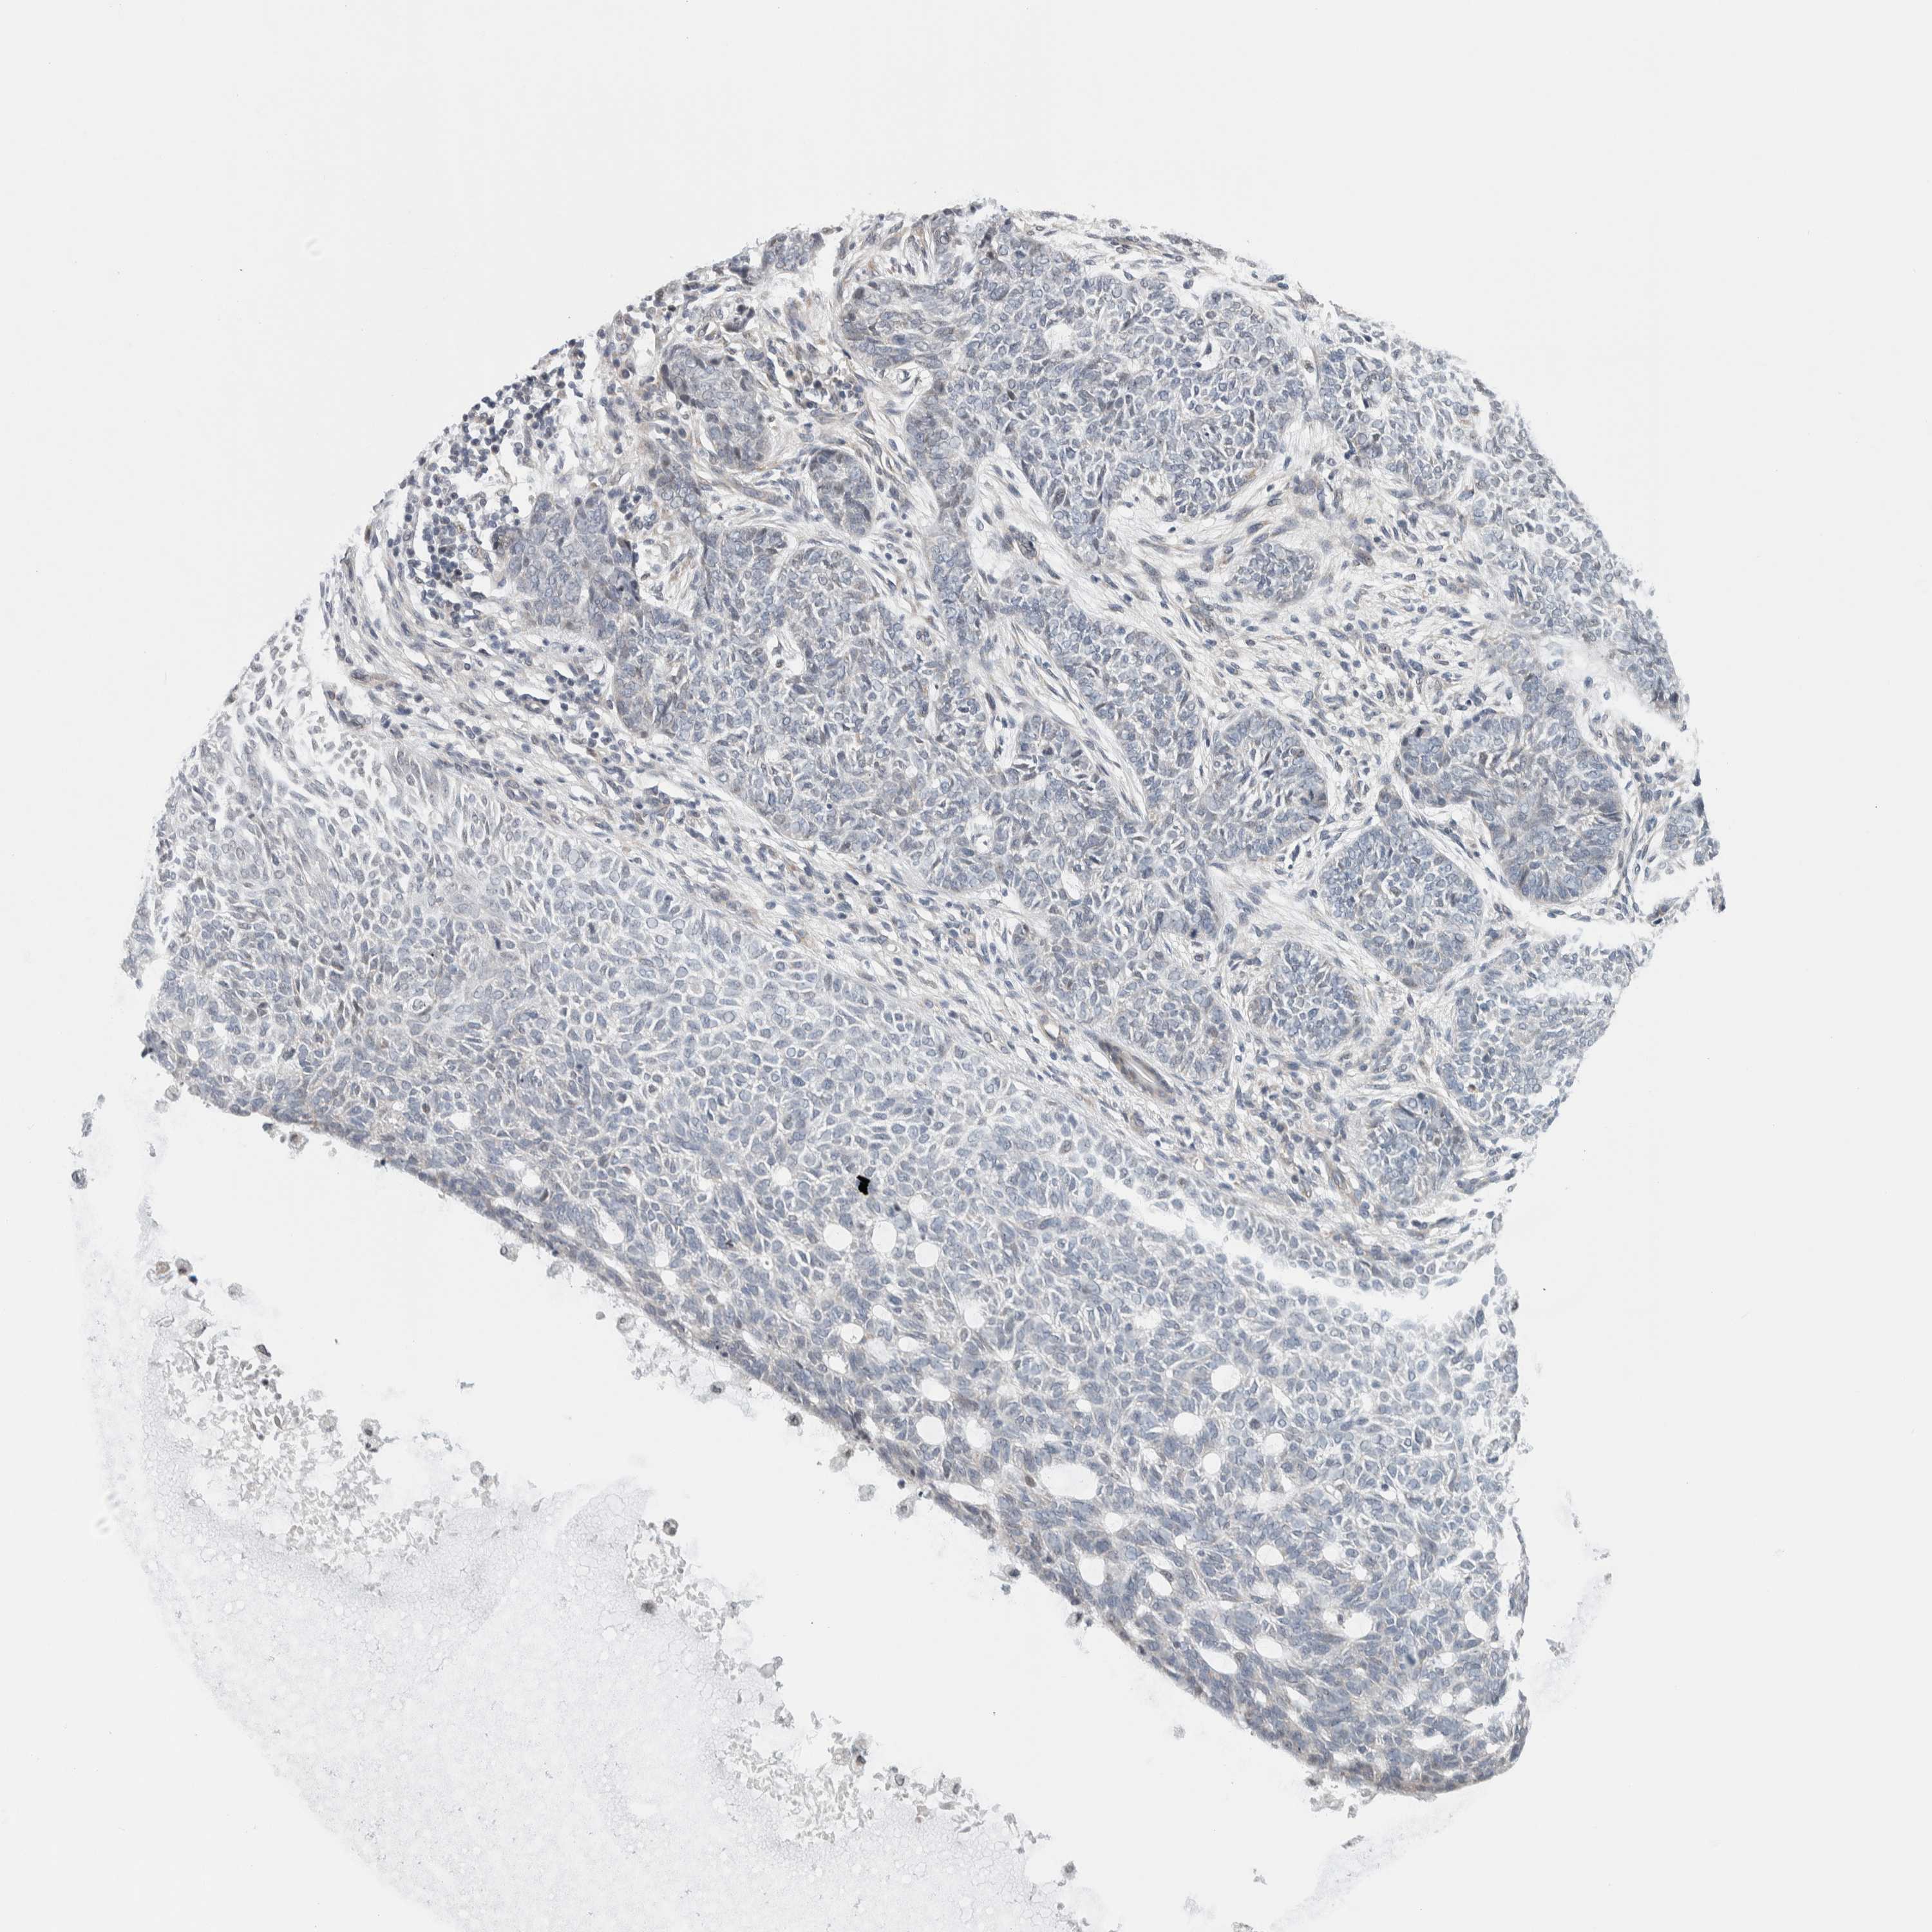

SKIN CANCER - Protein expressioni

A mouse-over function shows sample information and annotation data. Click on an image to view it in a full screen mode. Samples can be filtered based on level of antibody staining by selecting one or several of the following categories: high, medium, low and not detected. The assay and annotation is described here.

Antibody stainingi

Antibody staining in the annotated cell types in the current human tissue is reported as not detected, low, medium, or high, based on conventional immunohistochemistry profiling in selected tissues. This score is based on the combination of the staining intensity and fraction of stained cells.

Each image is clickable and will lead to virtual microscopy that enables deeper exploration of all samples and also displays staining intensity scores, fraction scores and subcellular localization as well as patient and tissue information for each sample.

Antibody HPA003278

Antibody CAB022450

Squamous cell carcinoma, NOS

Basal cell carcinoma